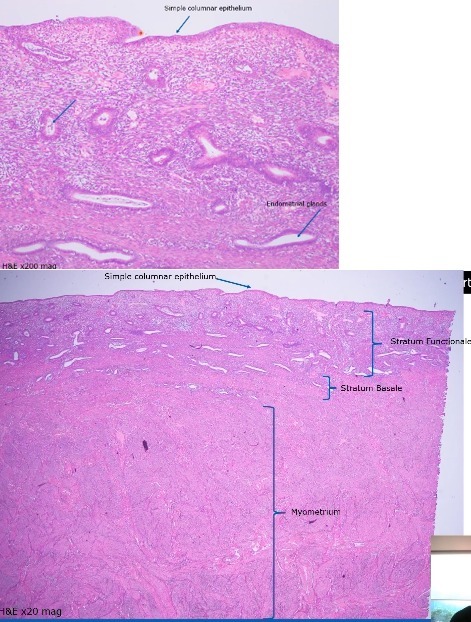

Uterus

A

Simple columnar epithelium

Stratum functionale contains endometrial glands (thickness depends on stage of menstrual cycle)

Stratum basale seperating functionale and myometrium

Myometrium very thick muscular layer